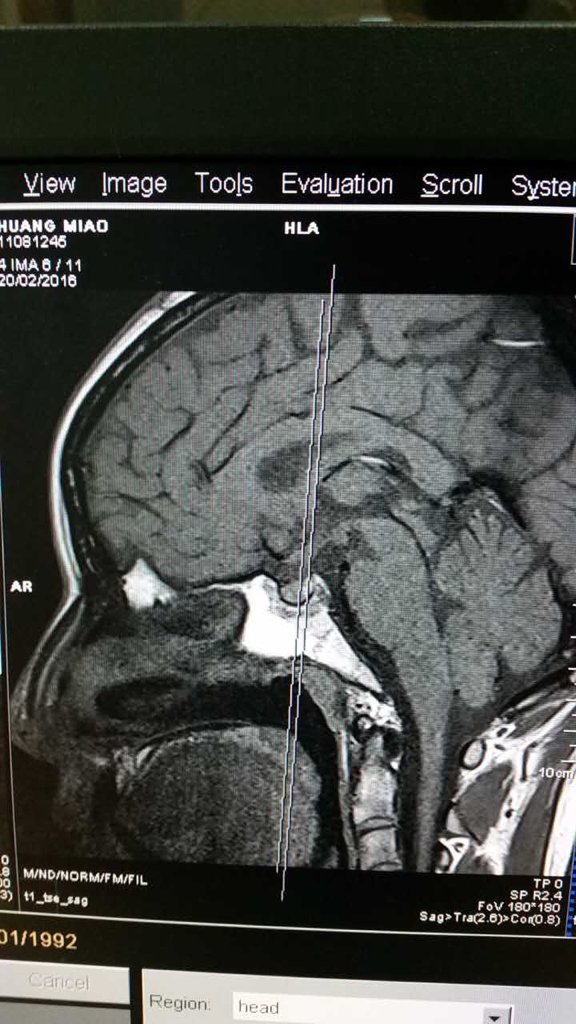

我28岁,未婚未育但因为月经不调,泌乳素200,于是做了垂体磁共振,麻烦懂的医生看看这片子里有没有

我28岁,未婚未育但因为月经不调,泌乳素200,于是做了垂体磁共振,麻烦懂的医生看看这片子里有没有瘤?或者异常?